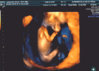

a to moje maleństwo:D